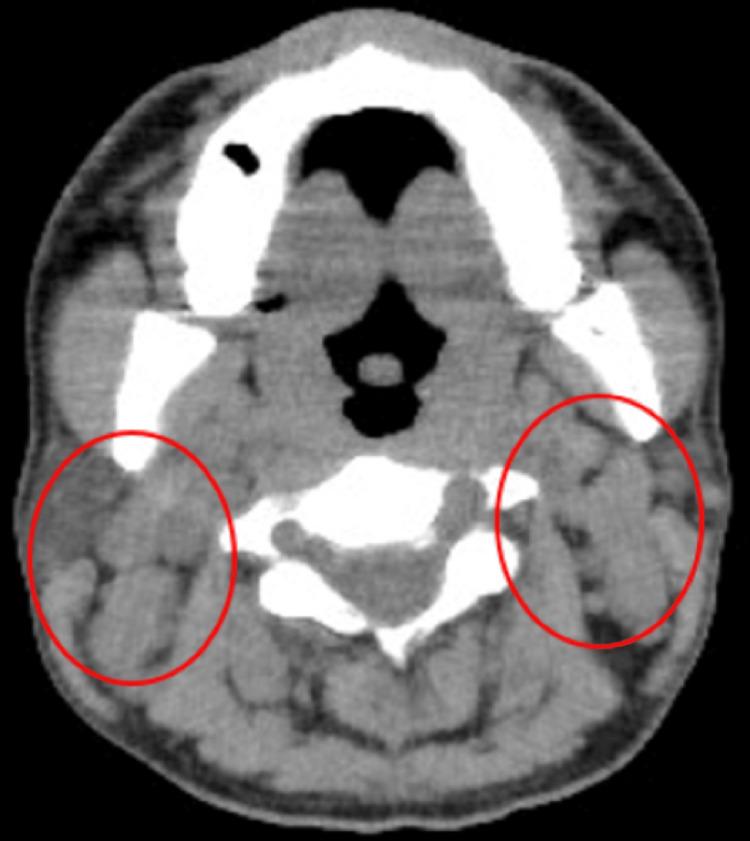

A 34-year-old man was referred to our hospital because of mild renal dysfunction and anemia. He had no specific preexisting medical conditions; his complaint was fatigue. Physical examination revealed several mobile, pinky head-sized (no tenderness) palpable lymph nodes on the bilateral neck. Blood biochemistry tests revealed anemia, renal dysfunction, increased inflammation, and a protein-albumin discrepancy. Immunological examination revealed polyclonal elevation of immunoglobulins (no shift in κ/λ ratio). A cervical lymph node biopsy was performed, and the pathological results showed numerous clusters of mature plasma cells (plasmacytic type), leading to the definitive diagnosis of idiopathic multicentric Castleman's disease (iMCD).